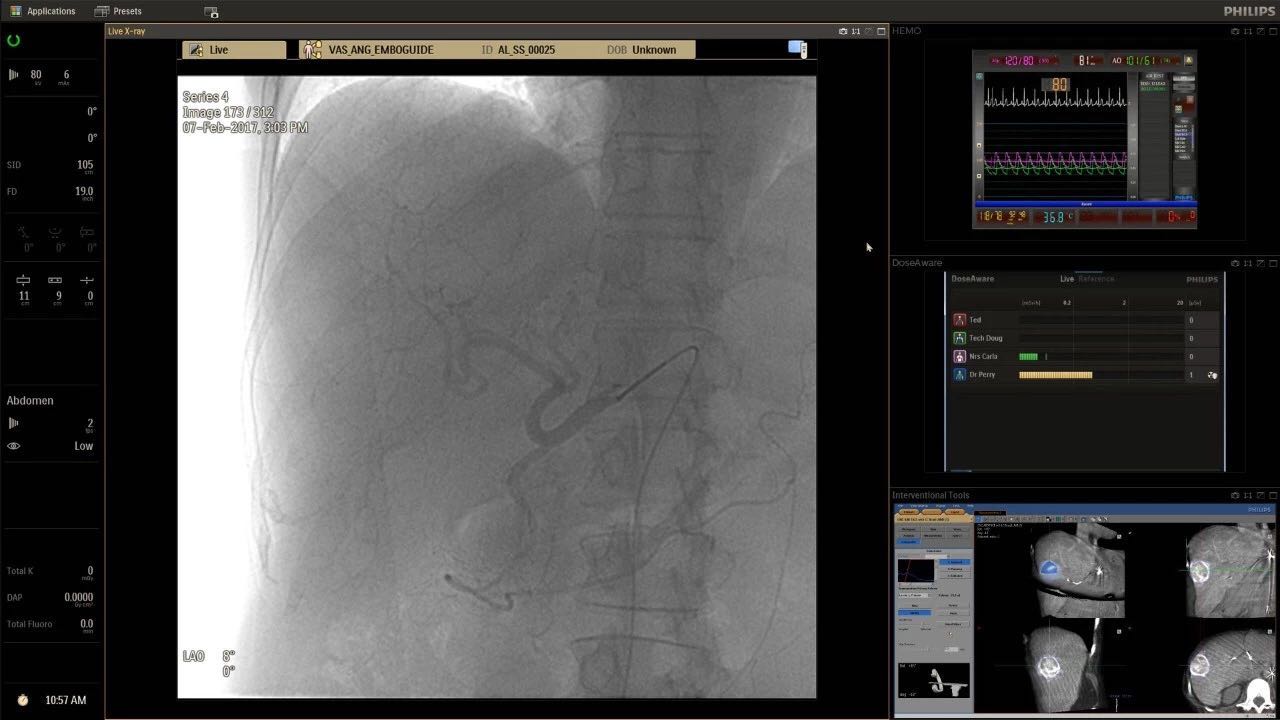

在日益復(fù)雜的干預(yù)期間,臨床醫(yī)生需要快速、輕松地可視化關(guān)鍵解剖結(jié)構(gòu)并確定手術(shù)過(guò)程中患者的變化。2019年1月17日,飛利浦宣布推出采用FlexArm的Azurion 7 C20,旨在提高圖像引導(dǎo)程序的定位靈活性。

帶有FlexArm的Azurion 7 C20 包含一系列創(chuàng)新技術(shù),使臨床醫(yī)生可以更輕松地在整個(gè)患者身上進(jìn)行二維和三維成像。當(dāng)臨床醫(yī)生移動(dòng)系統(tǒng)時(shí),圖像光束自動(dòng)保持與患者的對(duì)準(zhǔn),允許更一致的可視化并使他們能夠?qū)⒆⒁饬性谥委熒稀?/span>

飛利浦表示,采用FlexArm設(shè)計(jì)的Azurion 7 C20可提供卓越的靈活性和直觀的控制。該系統(tǒng)由智能運(yùn)動(dòng)引擎驅(qū)動(dòng),可在八個(gè)不同的軸上移動(dòng),所有這些軸均由其單個(gè)“Axsys”控制器控制。臨床醫(yī)生的模擬測(cè)試表明,該系統(tǒng)有可能顯著減少患者,工作人員和設(shè)備的重新定位,從而改善微創(chuàng)手術(shù)的可及性,包括通過(guò)患者手腕進(jìn)入身體的手術(shù)(橈動(dòng)脈入路),并降低患者的風(fēng)險(xiǎn)。無(wú)意中拔出電線和管子,以及節(jié)省大量時(shí)間。該系統(tǒng)非常適合混合手術(shù)室(OR),可滿足一個(gè)房間內(nèi)的多種專業(yè)需求,例如手術(shù)和血管內(nèi)手術(shù)的組合。

FlexArm在不少于8軸的情況下旋轉(zhuǎn),從而創(chuàng)建幾乎無(wú)限的靈活性來(lái)執(zhí)行成像,從頭部到腳部在左側(cè)和右側(cè)進(jìn)行2D和3D可視化。圖像光束保持與患者對(duì)齊,允許在旋轉(zhuǎn)或角度期間更好地可視化解剖結(jié)構(gòu)。使用Axsys運(yùn)動(dòng)控制系統(tǒng)輕松操作支架。